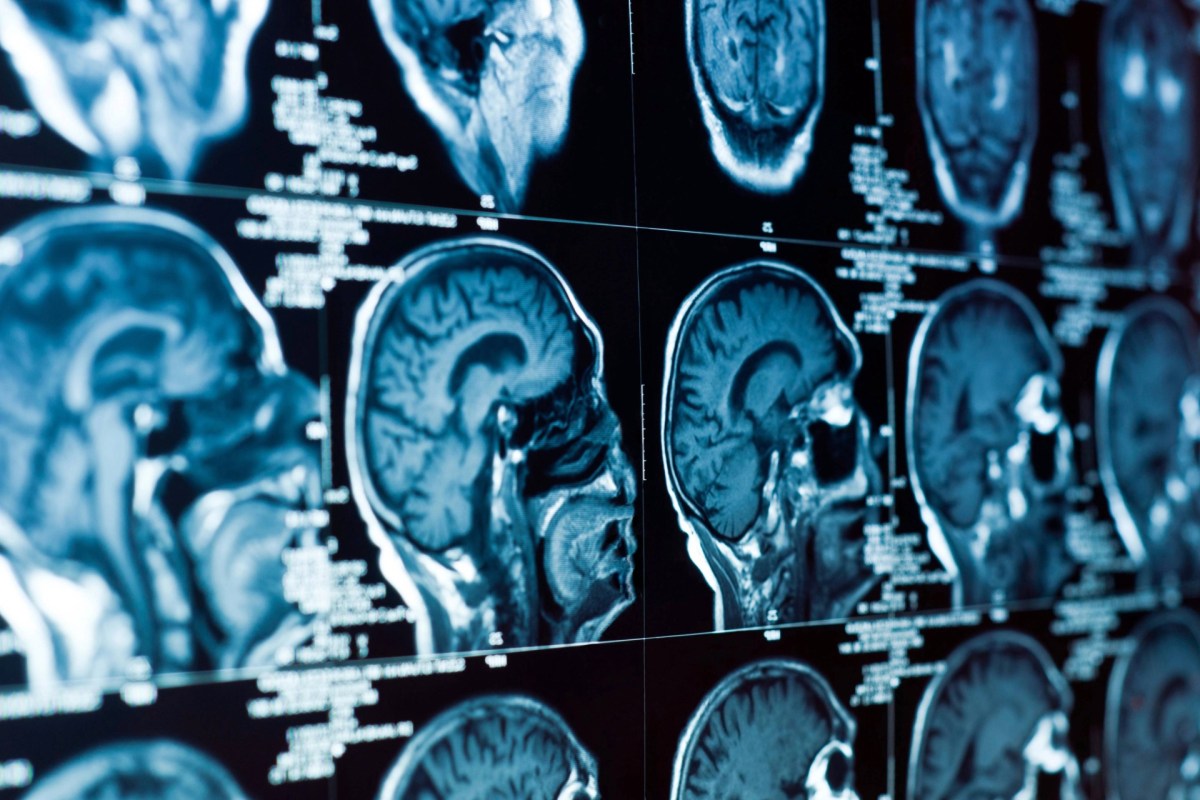

The exposed mice experienced anxiety-like behavior, impaired memory, and reduced attention. Brain scans showed that key brainwaves associated with learning and focus had shifted, and researchers discovered neuron damage in the hippocampus, the region responsible for memory. Chemical analysis confirmed changes in neurotransmitter systems and inflammation in brain tissue.